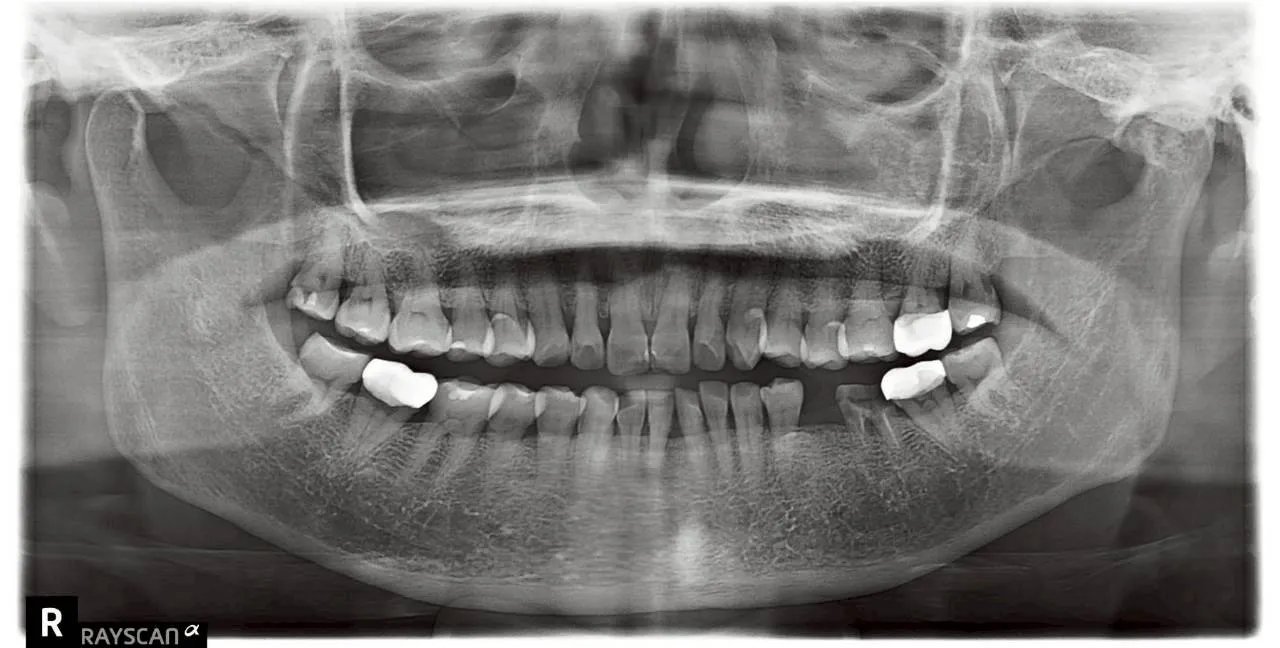

全口植牙重生紀實:找回咀疊的日常幸福

案例背景:那些被遺忘的味覺記憶

診療計畫:為生活品質開立的專業處方

謝昂儒醫師深知,植牙不只是補牙,更是重建生活。我們針對患者全口咬合不穩的現況,制訂了精準的植牙藍圖。

穩固基石的建立

• 力學回歸: 植體如基石般穩固,為全口提供對咬支撐。